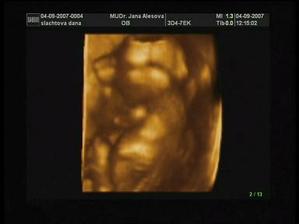

18.7 UTZ, kde nám krásně bilo srdíčko